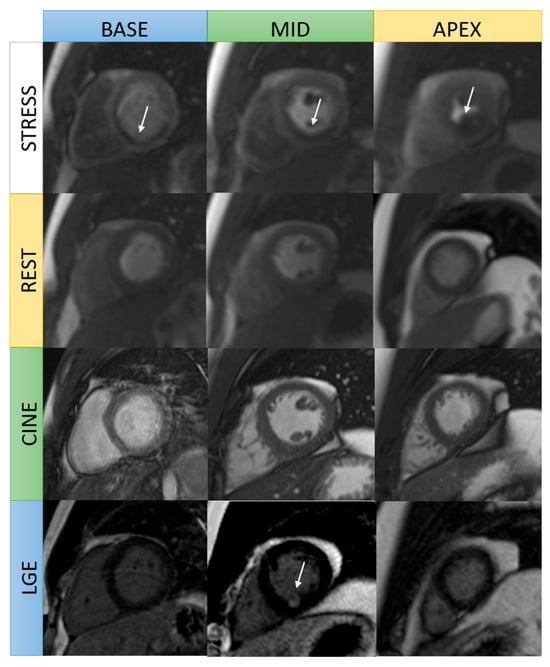

Figure 2.

Comparison of late gadolinium enhancement patterns in normal heart and ischemic heart disease.

Various LGE patterns can be used to differentiate between ischemic and nonischemic cardiomyopathies [30]. In ischemic heart disease, contrast uptake occurs along the ischemic wavefront from subendocardium to epicardium with varying degrees of transmurality, usually affecting one or more coronary territories (Figure 1) [6,30]. Transmural infarction extends through the entire wall of myocardium; non-transmural infarction has a sub-endocardial origin and involves <100% of wall thickness [30]. Non-ischemic cardiomyopathies, on the other hand, show mid-wall, sub-epicardial, or mixed LGE pattern, and are not confined to one coronary artery territory [31]. However, mid-wall LGE, a typical finding in non-ischemic cardiomyopathy, may also be present in an estimated 10% of patients with ischemic cardiomyopathy. This is indicative of extensive remodeling with severe LV dilation and systolic dysfunction and is strongly associated with ventricular arrhythmias and increased all-cause mortality, particularly when extensive or localized within the septum or lateral wall [32,33].